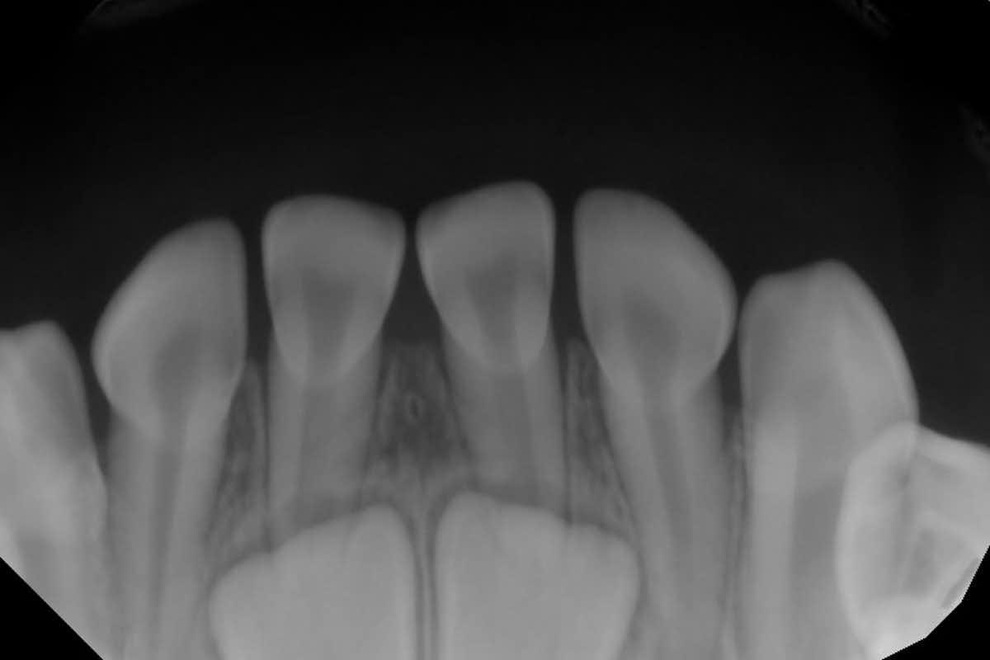

Men som de fleste pattedyr har vi mennesker bare to sett med tenner: Mælketenner, som begynner å komme frem når babyer er 6 til 8 måneder gamle. Deretter, når barn er mellom 5 og 12 år gamle, vil disse melketennene falle ut, og gi plass til de større permanente tennene.

At mennesker har to sett med tenner er en perfekt tilpasning til kroppens utvikling. Melketenner er relativt små og nødvendige for å passe inn i de små ansiktene og kjevene til små barn. Etter hvert som vi blir eldre, blir også ansiktene og kjevene våre større, noe som gir plass til flere og større tenner.

Permanente tenner (28, pluss muligheten for fire visdomstenner) er større enn melketenner, noe som hjelper oss å tygge mat mer effektivt, og passer for det varierte kostholdet til voksne.

Denne prosessen sikrer at tennene våre forblir i proporsjon med ansiktsstørrelsen vår når vi blir eldre, noe som hjelper oss med å opprettholde effektiv tyggeevne gjennom hele livet. Fortennene er ansvarlige for å bite og rive, mens jekslene er ansvarlige for å tygge mat i små biter før den svelges.

Et vanlig problem er det som kalles «trangstilling». Når en melketann trekkes ut, kan andre tenner rundt den forskyve seg inn i mellomrommet. Dette gir den permanente tannen utilstrekkelig plass til å komme ordentlig på plass, noe som fører til en tilstand som kalles trangstilling eller sammenpressede tenner.